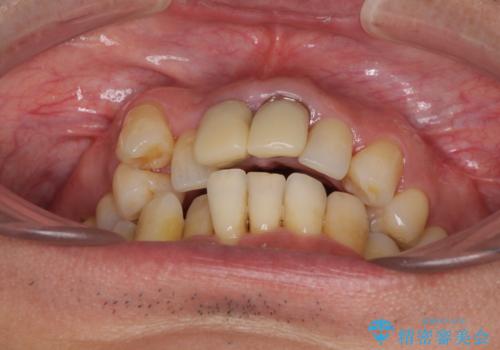

八重歯と突出感を改善 ワイヤー装置での矯正治療

- 八重歯を気にして来院された患者様です。

上顎前歯の突出感と右上の八重歯を気にされていたので、上顎左右の第一小臼歯2本を抜歯し、ワイヤー装置にて矯正治療を行うこととしました。

上顎前歯に装着されていた保険診療の前歯は見た目が気になるとのことであったので、矯正治療後にオールセラミッククラウンにて補綴治療を行うこととしました。

食いしばりにより奥歯がすり減っており、咬み合わせが定まるまで時間がかかりましたが、整った口もに仕上がりました。